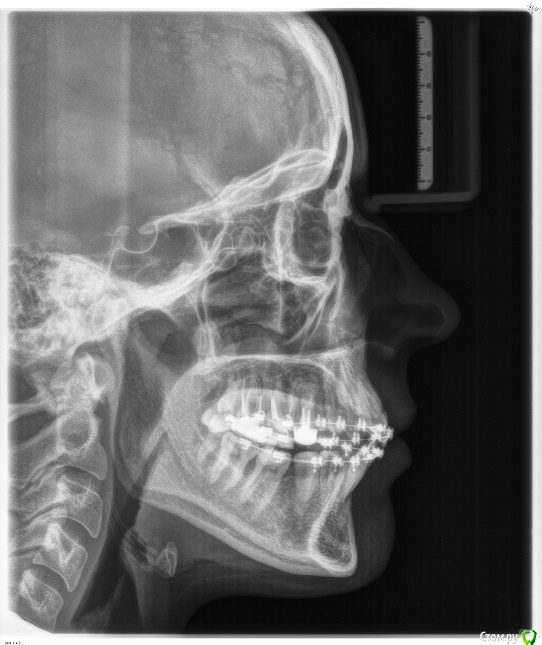

on1976 Опубликовано 18 июля, 2019 Поделиться Опубликовано 18 июля, 2019 (изменено) Добрый день!У меня огромная проблема,Я попала в чудовищную ситуацию в лечении зубов брекетами и вот это длится уже 4 года.По итогу на сегодняшний день, у меня проблемы со здоровьем, депрессия, очень изменилось лицо и прочие последствия.Случайно наткнулась на статьи о "ALF ортодонтия" и прочла об основателе ортокраниодонтии и данного метода в России Алексее Олеговиче Савинове, Skip, но найти информацию и записаться на приём я нигде не могу. А мне важно его мнение по моей ситуации. Сил моих уже больше нет лечиться поскольку улучшений нет. Помогите найти координаты и записаться на приём Савинову.Я прикрепляю файлы ренгена. Может кто выразит своё мнение. (приложенные сними на начальном этапе лечения, сейчас изменения есть, но общая картина изменилась в худшую сторону.)Ортокраниодонтия как последняя надежда! Буду благодарна если получу от вас обратную связьмой тел 89272818180e-mail: on1976@yandex.ru С уважением Сальникова Ольга. Изменено 18 июля, 2019 пользователем on1976 Ссылка на комментарий

Force Опубликовано 20 июля, 2019 Поделиться Опубликовано 20 июля, 2019 Ортокраниодонтия - это альтернативная ортодонтия, то есть по факту - те же возможности, но другими методиками. В вашем случае прямые показания к ортогнатической хирургии. В Астрахани есть хороший ортодонт - пишите в личку Ссылка на комментарий

on1976 Опубликовано 23 июля, 2019 Автор Поделиться Опубликовано 23 июля, 2019 Ортокраниодонтия - это альтернативная ортодонтия, то есть по факту - те же возможности, но другими методиками. В вашем случае прямые показания к ортогнатической хирургии. В Астрахани есть хороший ортодонт - пишите в личкуТак -то оно так, но в течении 4 лет ношения брекетов, положение стало меняться, и я задумалась о возможности решения альтернативным способом, перекос верхней части стал меньше. Возможно это можно решить ALF капой? Ссылка на комментарий